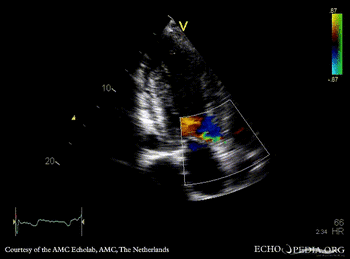

A3CH A3CH with Color Doppler

Suprasternal view: Collor Doppler, high velocity flow in left ventricle outflow tract Continuous-wave signal of high flow in left ventricle outflow tract